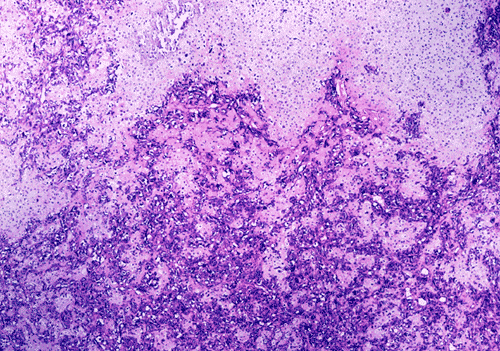

At low power magnification (Panel A and B), the tumor seems to have two distinct components. The first is a highly cellular, basophilic, background stroma. The second is islands of well-demarcated, pale bluish chondroid, hypocellular areas reminiscent of hyaline cartilage. Together, these two components impart a so-called "white clouds in blue sky" histologic appearance. At medium- and high power magnification (Panel C and D), the lacuna in the chondroid areas are well appreciated which helps to confirm the cartilaginous nature of these pale islands. Please note the impressive nuclear pleomorphism in the neoplastic chondrocytes (Panel D).

Grossly, mesenchymal chondrosarcoma typically appears as a circumscribed, lobulated, solid mass with a soft, fleshy, grey-white to gray-pink cut surface. Scattered deposits of cartilage and/or bone of varying size may be grossly recognized, and areas of hemorrhage and necrosis may be present. Tumor size is variable with reported tumor diameters ranging from 3 - 37 cm. Microscopically, mesenchymal chondrosarcomas are biphasic tumors composed of sheets of round to spindle-shaped primitive mesenchymal cells surrounding discrete islands of hyaline cartilage. The proportions of primitive and cartilaginous elements vary widely among tumors and even within different areas of the same tumor. Cartilaginous differentiation ranges in degree and extent from small foci with high-grade nuclear features to large areas of well-differentiated cartilage. The primitive mesenchymal component is highly vascular, typically containing large numbers of highly branched vascular channels (the so-called “hemangiopericytoma-like pattern”).